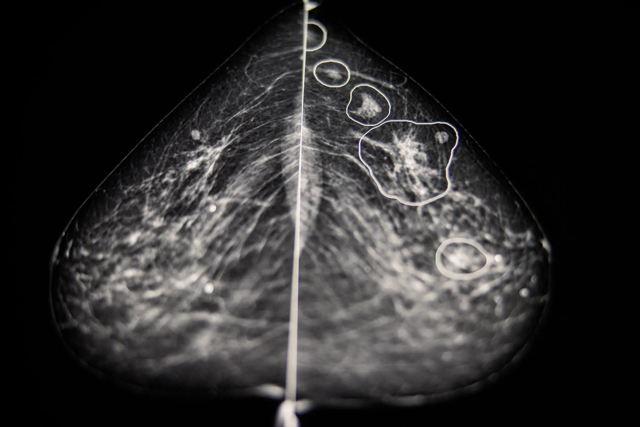

In Ungheria, per esempio, cinque cliniche che eseguono più di trentacinquemila screening per il cancro al seno usano l’AI dal 2021.

Questa AI è sviluppata da una società inglese chiamata Kheiron Medical Technologies.

Kheiron ha istruito il suo modello di intelligenza artificiale con cinque milioni di mammografie ottenute da cliniche in Ungheria e Argentina e ha impiegato dodici radiologi in carne e ossa per aiutare l’AI a riconoscere un cancro al seno in via di sviluppo in base alla forma, alla densità, alla posizione e ad altri vari fattori riconoscibili nelle mammografie.

Nel 2022, questa tecnologia è stata testata su 275.000 casi di cancro al seno.

E l’azienda suggerisce che la sua AI è in grado di offrire la stessa performance di un radiologo umano quando è usata come cassa di risonanza per i dottori.

Funziona così. Per ogni nuova mammografia, i radiologi esprimono la loro opinione. A questo punto l’immagine viene passata all’AI per una seconda opinione. E qui l’AI conferma la diagnosi dei radiologi o suggerisce di controllare meglio un’area specifica della mammografia.

In ventidue casi, come ha riportato il New York Times e molte altre pubblicazioni, l’AI ha identificato un cancro al seno che è sfuggito a radiologi con venti anni di esperienza, e ci sono altri quaranta casi che devono essere ancora verificati.

Questa tecnologia è così promettente che molte altre cliniche e ospedali negli Stati Uniti, nel Regno Unito, in Europa ne stanno valutando l’adozione.